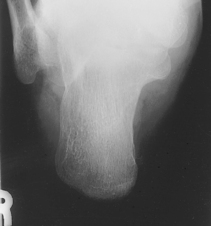

• Supine or seated, dorsiflex foot to as near vertical position as possible. If possible, have patient pull on gauze as shown. (This may be painful for patient to maintain, don’t delay!)